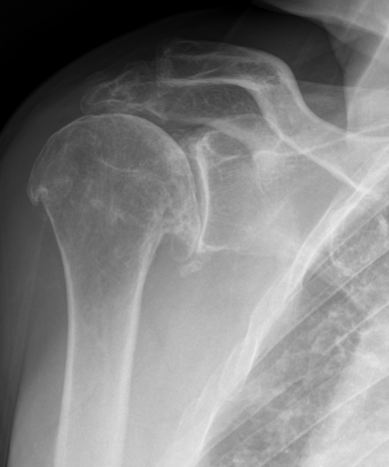

Rotator Cuff Arthropathy

On the other hand, a reverse shoulder replacement is used when the rotator cuff is damaged or nonfunctional. In this procedure, the normal anatomy of the shoulder is reversed. The ball is placed on the shoulder blade (glenoid), and the socket is placed on the upper arm bone (humerus). This reversal changes the mechanics of the shoulder, allowing the deltoid muscle to take over the function of the rotator cuff, helping stabilize the arm for overhead movement. Reverse shoulder replacement is typically recommended for patients with irreparable rotator cuff tears, where the rotator cuff cannot be successfully repair, or rotator cuff arthropathy, which is a type of arthritis that develops due to chronic rotator cuff dysfunction. Patients who have massive rotator cuff tears or rotator cuff arthropathy can no longer properly support the shoulder joint. It is also beneficial in cases of proximal humerus fractures or rhuematoid arthritis that have caused significant damage to the joint.